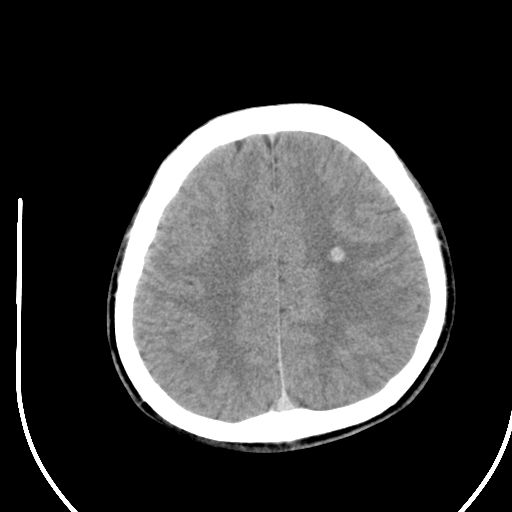

标题: CT28158:男,27Y。头痛数月,左顶叶血管瘤。 [打印本页]

标题: CT28158:男,27Y。头痛数月,左顶叶血管瘤。

考虑左顶叶海绵状血管瘤,建议mr检查。

左侧额叶海绵状血管瘤可能性大;建议行mri检查。

考虑血管畸形,因其周可见水肿,不除外感染性病灶。建议mri检查。